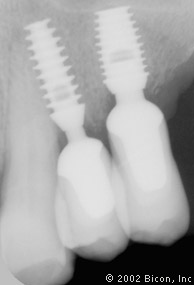

74. | X光片显示两颗最近戴入的双尖牙一体化基台冠。 |